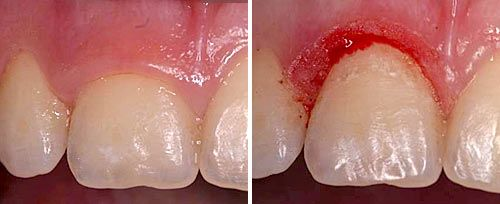

硬组织切除

硬组织切除:激光能够逐层切割去除硬组织,相比传统手机,操作更方便、更精准。

口腔激光怎么治疗口腔特色诊疗——激光治疗_https://www.jmylbn.com_新闻资讯_第11张

激光冠延长术前后对比图